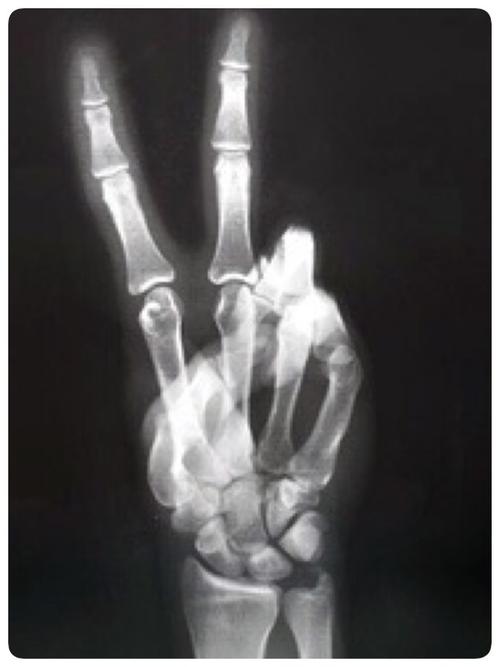

求v字手的x光片或这张图原图

x光手指图片

手指x光图

手指x光